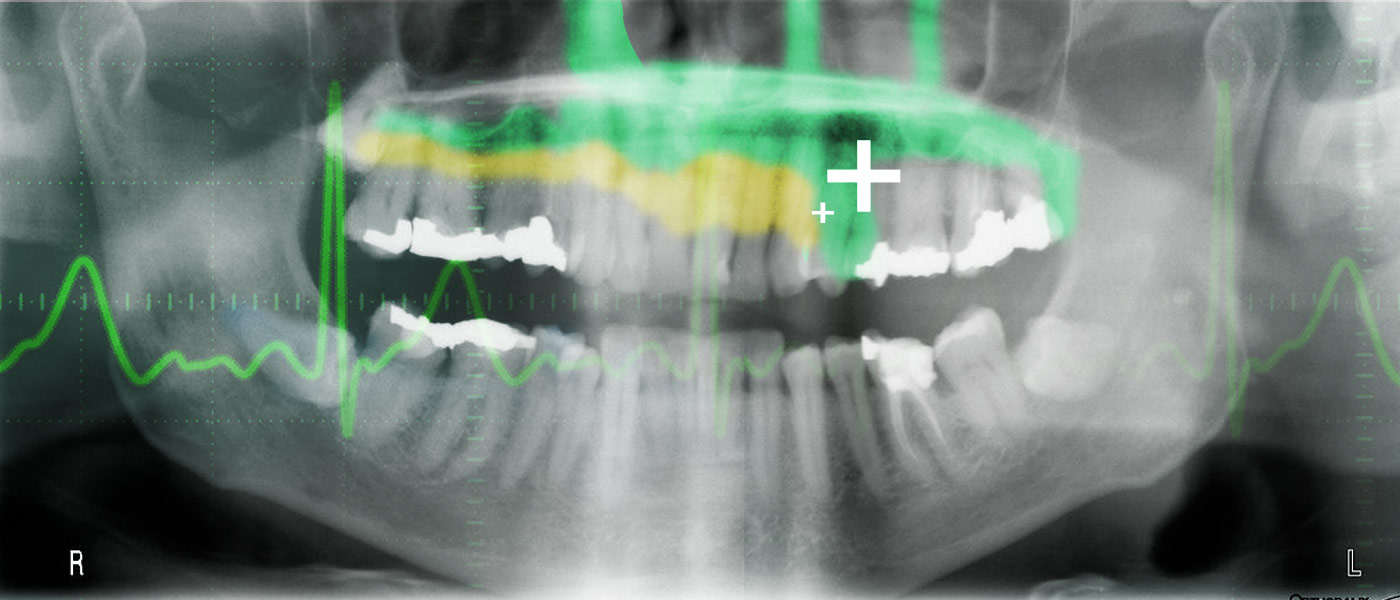

Aside from a less traumatic experience in the chair, there are many benefits of this type of dentistry. “Existing dental fillings are toxic to cells and are therefore incompatible with pulp tissue inside the tooth,” said Adam Celiz, a research fellow from the University of Nottingham. “In cases of dental pulp disease and injury a root canal is typically performed to remove the infected tissues.”

Celiz describes the process, “We have designed synthetic biomaterials that can be used similarly to dental fillings but can be placed in direct contact with pulp tissue to stimulate the native stem cell population for repair and regeneration of pulp tissue and the surrounding dentin.”